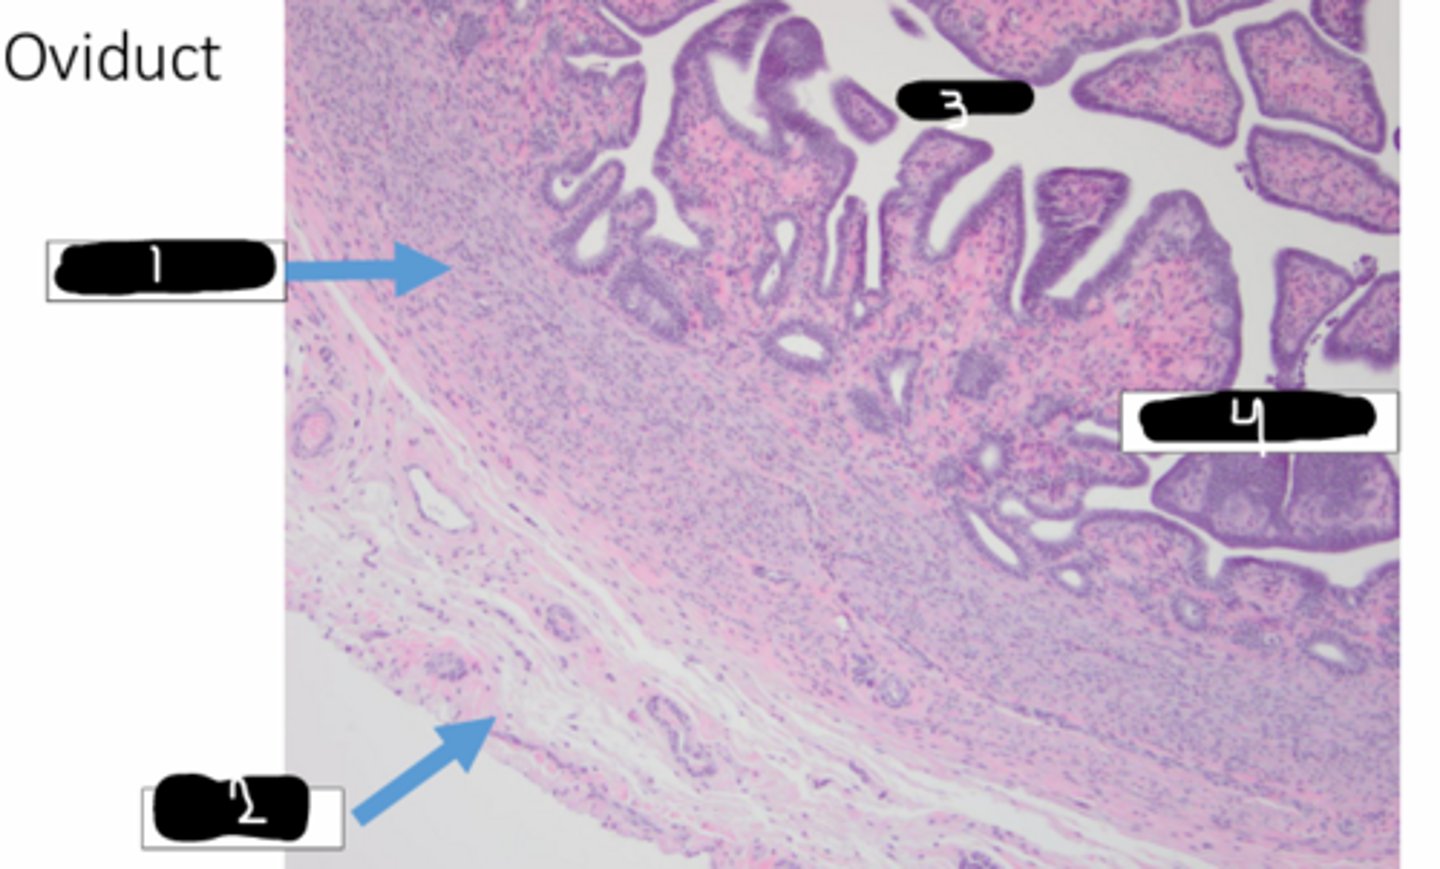

muscularis

1

serosa

2

lumen

3

endometrium

4

lamina propria

this is the oviduct. identify black

simple columnar, cilia

this is the oviduct. identify red